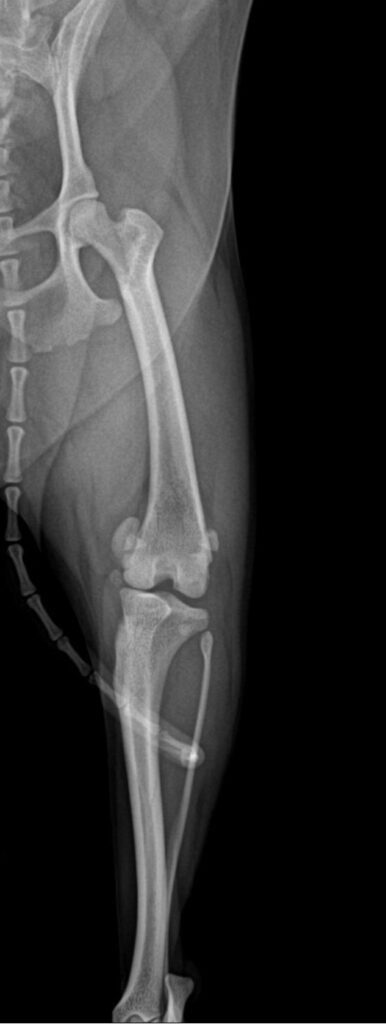

슬개골 촉진 검사에서 양측 슬개골 모두 내측 탈구가 확인되었고, 우측은 2–3기, 좌측은 4기로 진단되었습니다. 엑스레이 검사에서도 무릎뼈가 대퇴골 고랑을 벗어나 내측에 위치한 모습이 명확히 관찰되었습니다.

수술 전 X-ray 사진 / 출처: 미래동물의료센터

환자는좌측 슬개골 탈구의 진행 정도가 매우 심한 상태였기 때문에 보호자 상담 후 좌측 슬개골 탈구 수술을 진행하기로 결정했습니다. 수술 전에는 마취 전 혈액검사와 흉부 방사선 검사 실시하였습니다.

수술 전 방사선사진 / 출처: 미래동물의료센터

수술 후 엑스레이에서는 슬개골이 정상적으로 대퇴골 고랑 안에 안정적으로 위치한 것이 확인되었습니다.

수술 후 x-ray 사진 / 출처: 미래동물의료센터

수술 후 촬영한 엑스레이에서 수술 전에는 내측으로 벗어나 있던 슬개골이 대퇴골 고랑 안에 정상적으로, 안정적으로 위치해 있는 것이 확인되었습니다.

이는 수술의 구조적 교정이 잘 이루어졌다는 중요한 지표입니다. 환자는 입원 치료를 마친 뒤 무사히 퇴원했고, 현재는 통원 치료와 회복 과정을 안정적으로 이어가고 있습니다.